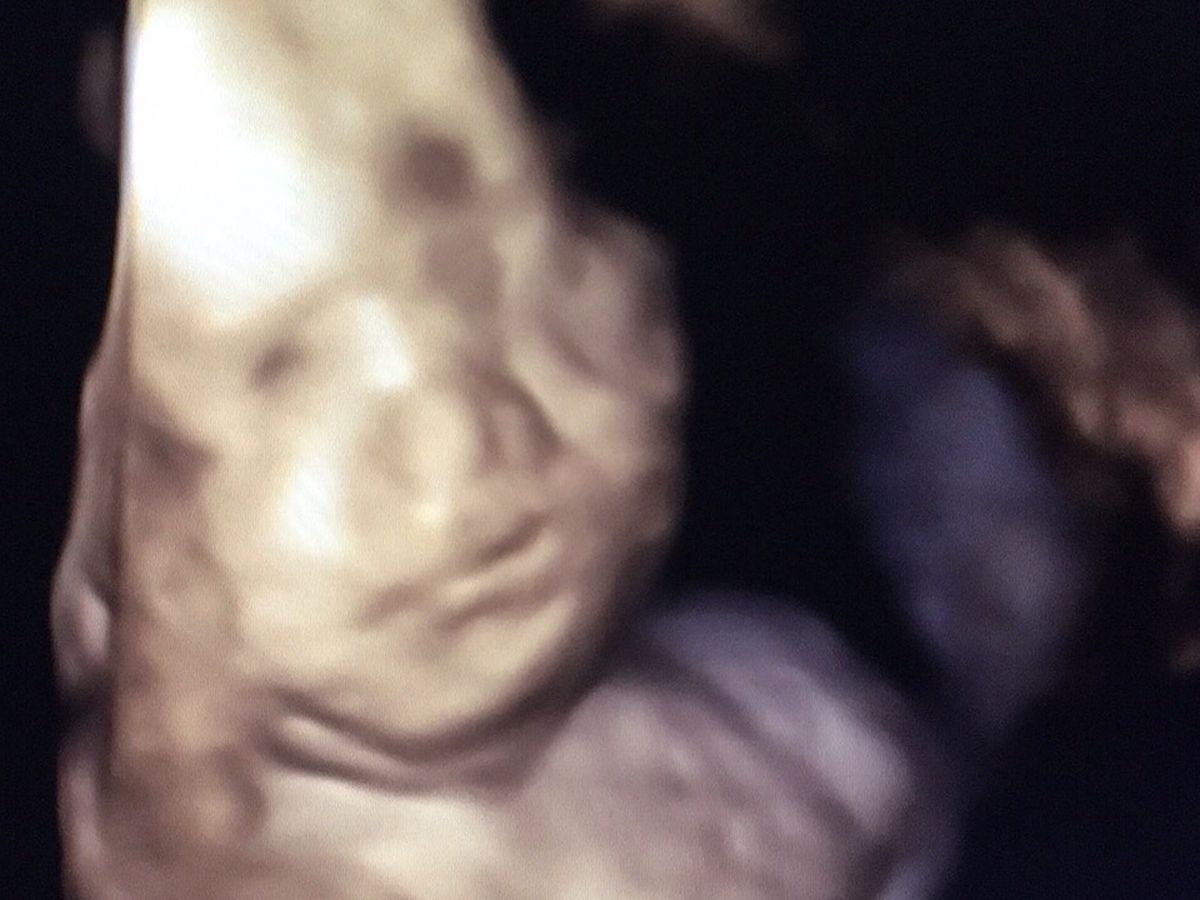

On July 25th we were told our sweet little girl had Potter's Sequence, which is where no kidneys or (sometimes a partial) bladder form. These conditions are not what causes the baby to pass away, what does cause it is the lack of amniotic fluid not giving their lungs a chance to develop and ultimately the baby passes from pulmonary hypo.

Miguel and I as parents are completely terrified for our baby girl, and want to help her as much as we possibly can. In Oklahoma they do not have the capabilities to help give amnioinfusions to help her. John Hopkins hospital has a scientific study available that she would be able to receive fusions and have the chance at life. She would be on dialysis due to the lack of kidneys, but would by the age 2 be a candidate for a kidney transplant. We desperately want to give her a chance to be on Earth.